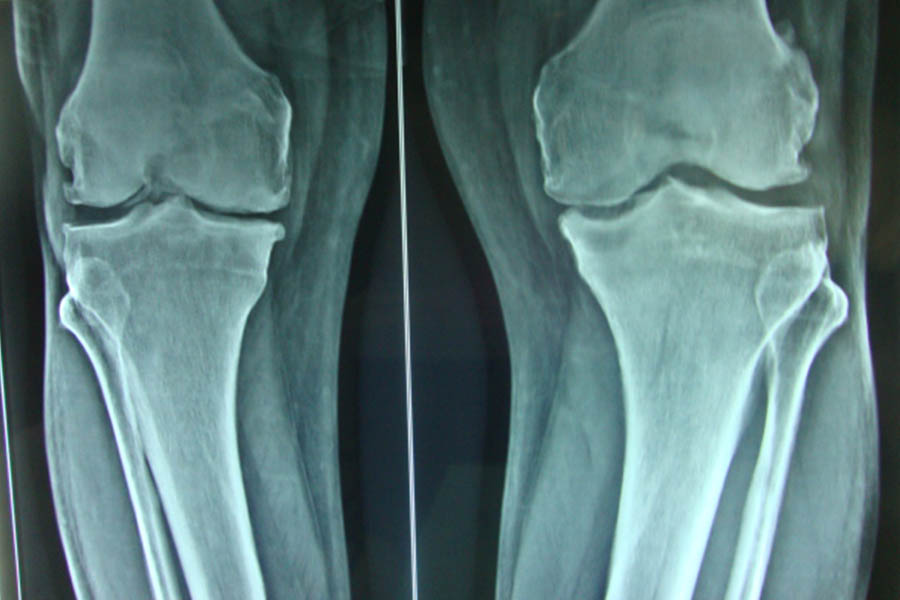

Total Knee Replacement

Case 1